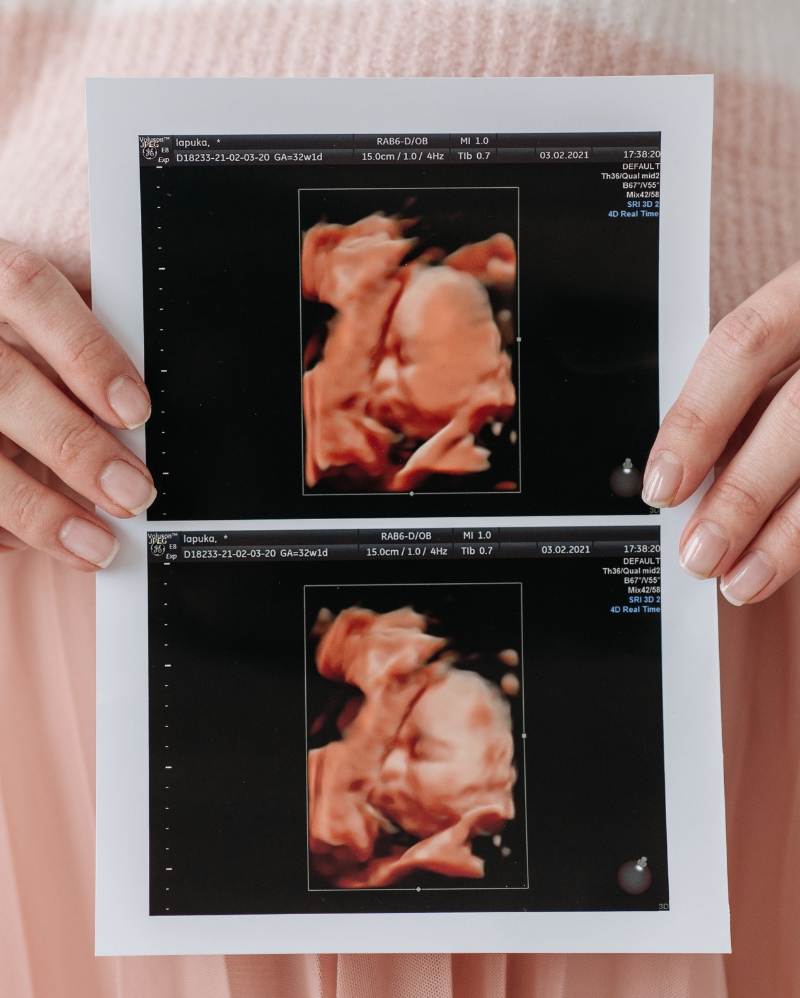

Ultrasonido Estructural

Este sirve para valorar el desarrollo cerebral y cardiaco adecuado para las semanas 18 a 22 de embarazo.